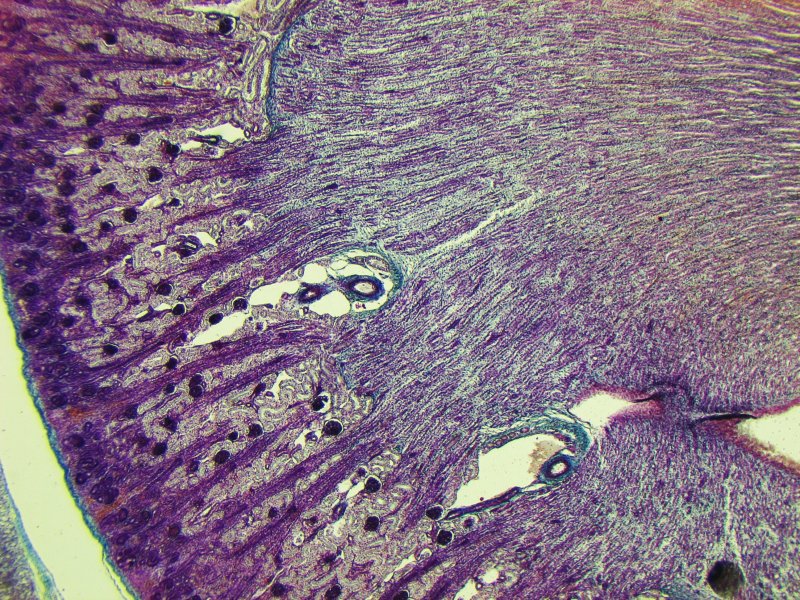

rana esculenta, Planachromat 16/0,35, Kpl 8x, Canon A95

Man sieht recht deutlich die Struktur der Kanäle. Allerdings bildet die Niere im Wesentlichen ein ganzes Netzwerk, das aus verschiedenen Kanälen besteht. In manchen der Kanäle fliesst das aufzubereitende Blut, dass allmählich quasi per Osmose gefiltert wird, während Urin in weiteren Kanälen gebildet, in wieder weiteren Kanälen aufkonzentriert und abgeleitet wird. Die Flüssigkeit, die beim Aufkonzentrieren anfällt, wird wieder in den Blutkreislauf zurückgeführt. Also - ebenfalls durch entsprechende Kanäle, wer in diesem Gewirr den Durchblick hat, kann es vielleicht zuordnen. Das Prinzip ist bei Hund, Katze, Maus und Mensch ähnlich, die Ausgestaltung aber deutlich anderst. So sieht es bei einer neugeborenen Katze aus:

Man erkennt als ein wesentliches "Designmerkmal" der Niere kreisrunde Gebilde, Glomeruli - "Knäuel", die auch beim Frosch in den obigen Bildern in verminderter Zahl vorkamen. Hier, bei der (neugeborenen) Katze sind schon mehrere zu sehen: